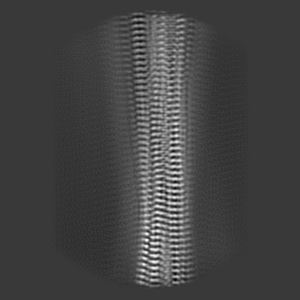

Structure of pathological TDP-43 filaments from ALS with FTLD

Sample: Pathological TDP-43 filaments extracted from the frontal cortex of an individual that succumbed to ALS with FTLD.

Structure of pathological TDP-43 filaments from ALS with FTLD.

Arseni D , Hasegawa M , Murzin AG, Kametani F , Arai M , Yoshida M, Ryskeldi-Falcon B

(2022) Nature , 601 , 139 - 143